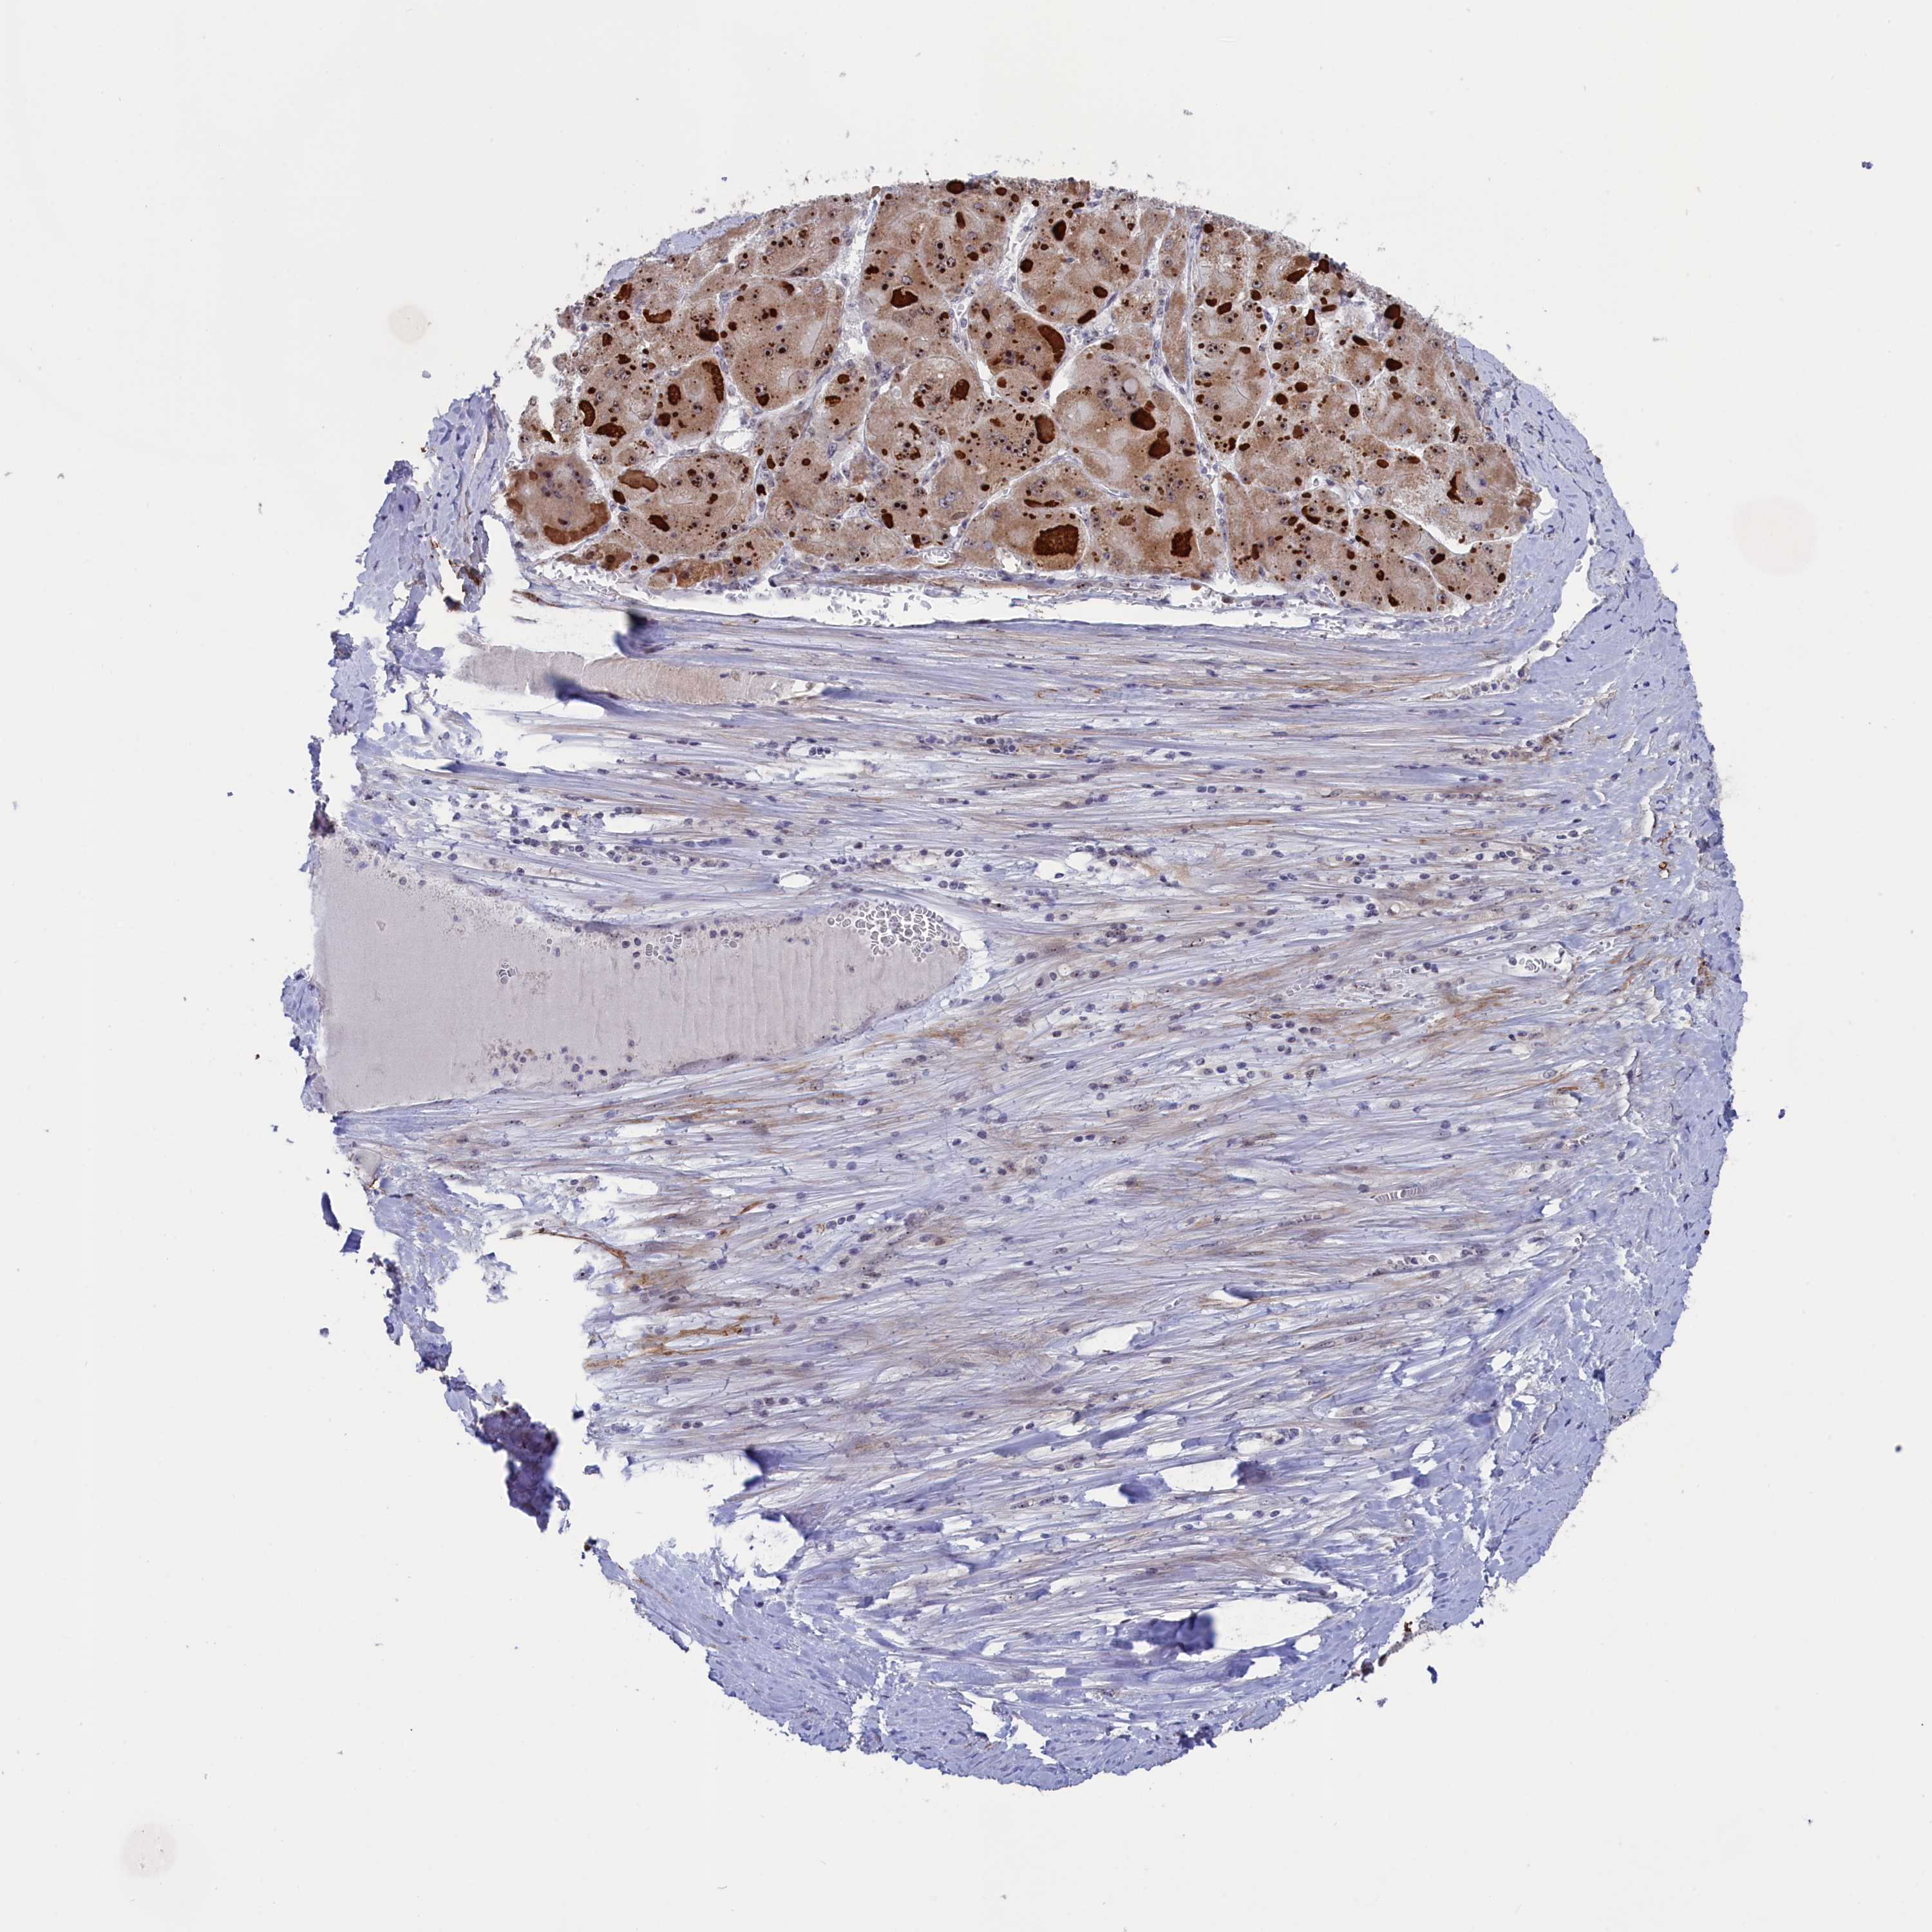

LIVER CANCER - Protein expressioni

A mouse-over function shows sample information and annotation data. Click on an image to view it in a full screen mode. Samples can be filtered based on level of antibody staining by selecting one or several of the following categories: high, medium, low and not detected. The assay and annotation is described here.

Note that samples used for immunohistochemistry by the Human Protein Atlas do not correspond to samples in the TCGA dataset.

Antibody stainingi

Antibody staining in the annotated cell types in the current human tissue is reported as not detected, low, medium, or high, based on conventional immunohistochemistry profiling in selected tissues. This score is based on the combination of the staining intensity and fraction of stained cells.

Each image is clickable and will lead to virtual microscopy that enables deeper exploration of all samples and also displays staining intensity scores, fraction scores and subcellular localization as well as patient and tissue information for each sample.

Antibody HPA043265

Staining

High

Medium

Low

Not detected

Intensity

Strong

Moderate

Weak

Negative

Quantity

>75%

75%-25%

<25%

None

Location

Nuclear

Cytoplasmic/membranous

Cytoplasmic/membranous,nuclear

Cholangiocarcinoma

Carcinoma, Hepatocellular, NOS